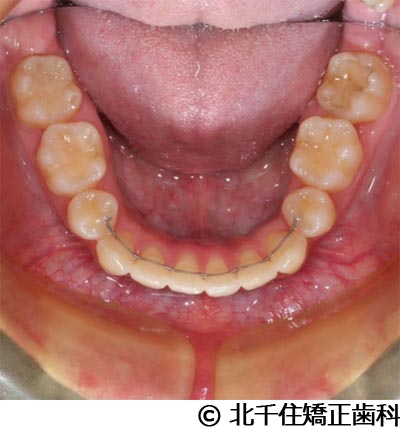

【症例5】上顎前突

- 治療前

- 治療後

- 治療名

- 上顎前突

- 費用

- 1,263,600円(税込)

- 期間

- 2年8ヵ月

- 治療回数

- 32回

- 通院頻度

- 1ヵ月ごと

- 年齢

- 13歳3ヵ月(初診時)

治療内容

患者様の症状

主訴:出っ歯

治療方法

骨格性の上顎前突、ヘッドギアを併用して上下顎第一小臼歯4本抜歯してワイヤー矯正。

治療結果

骨格性上顎前突に対し、ヘッドギアおよび抜歯を併用した矯正治療により歯列および咬合関係の調整を行った症例である。

治療後は保定装置を使用し、歯列および咬合の安定維持を目的として定期的な経過観察を行っている。

※治療結果は個人差があります。

治療を行う上での注意点(リスク・副作用)

歯磨き不良に伴うカリエスや歯周病、歯根吸収など。